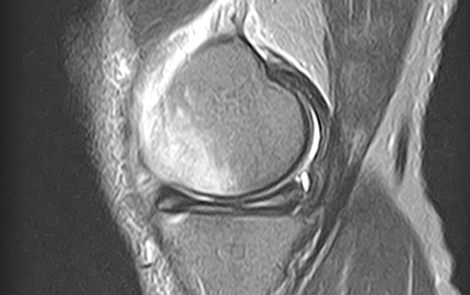

MRI

MRIとは磁気共鳴画像撮影法のことで正式には「Magnetic(磁気) Resonance(共鳴) Imaging(画像)」といいます。

1.5テスラMRI装置Vantage Elan(キャノンメディカルシステムズ製)を導入しておりレントゲン検査では評価しづらい骨の内部や軟部領域の精査が可能で、脊椎・四肢など整形外科領域の幅広い部位の検査を行っています。撮影部位にもよりますが検査には約20~40分ほど時間がかかります。低侵襲で安全な検査ですが強い磁気を使うので金属類は外して検査を行います。通常予約待ちの多いMRI検査ですが当院では医師の指示のもと初診時の当日検査も可能でスムーズかつ的確な診断、検査待ちの解消にも努めています。